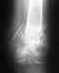

1 июля 2011 года я сломала бедро. Перелом со смещением. 4 дня на вытяжке, потом операция остеосинтеза, прошло уже 1,5 месяца.

Для ответа на вопрос о допустимой нагрузке надо хотя бы увидеть, какой именно перелом бедра, и какой остеосинтез сделан, и как он сделан.